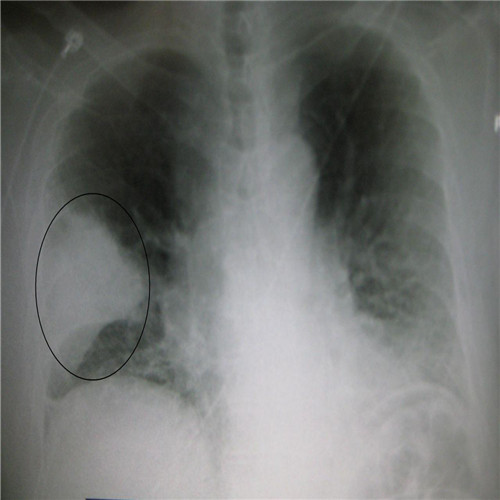

呼吸道感染胸腔積液胸片下觀察

呼吸道感染胸片檢查